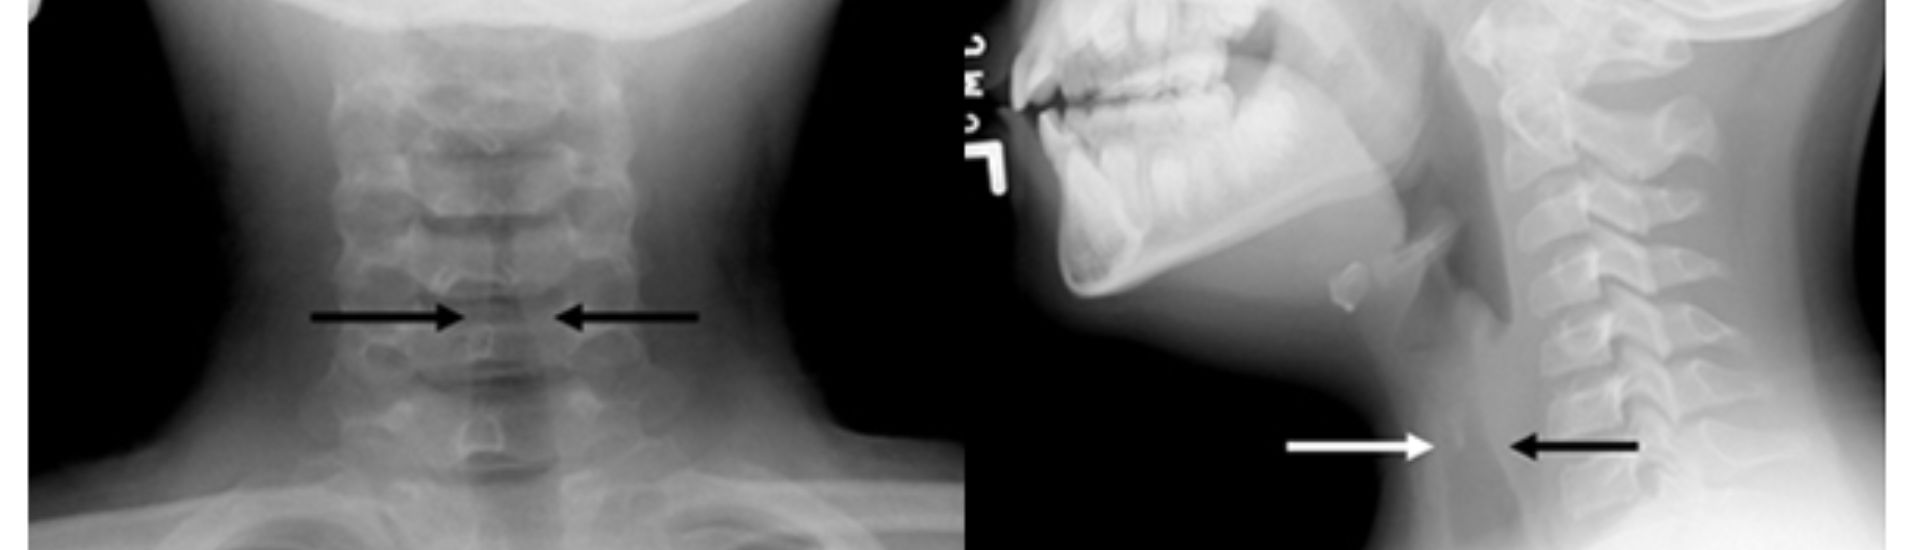

L’Rx Laringe è una tecnica radiologica che consente di ottenere immagini dettagliate della laringe e delle sue componenti principali, come le corde vocali e la glottide. Questo esame permette agli specialisti del Poliambulatorio S-Medical Group di Sora di esaminare con precisione eventuali anomalie strutturali o funzionali, rendendolo indispensabile per chi presenta disturbi vocali, difficoltà respiratorie o sintomi persistenti legati alla deglutizione.

L’Rx Laringe prevede l’ingestione di una piccola quantità di mezzo di contrasto da parte del paziente, che consente di evidenziare al meglio le strutture della laringe durante l’esame. Successivamente, vengono acquisite diverse immagini mentre il paziente compie azioni vocali specifiche, come la pronuncia di determinati suoni. Questo consente agli specialisti di osservare il comportamento dinamico delle corde vocali e di identificare eventuali disfunzioni o lesioni presenti.